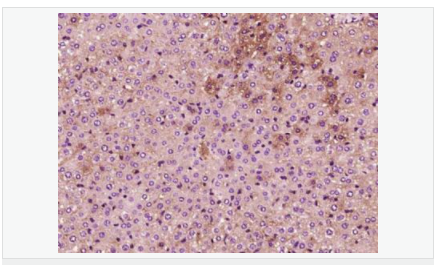

交叉反應(yīng):Human,Mouse,Rat(predicted:Phosphotyrosine) 推薦應(yīng)用:IHC-P,IHC-F,ICC,IF

| 產(chǎn)品應(yīng)用 | IHC-P=1:100-500 IHC-F=1:100-500 ICC=1:100-500 IF=1:100-500 (石蠟切片需做抗原修復(fù)) not yet tested in other applications. optimal dilutions/concentrations should be determined by the end user. |

| 細(xì)胞定位 | 細(xì)胞核 細(xì)胞漿 細(xì)胞膜 |